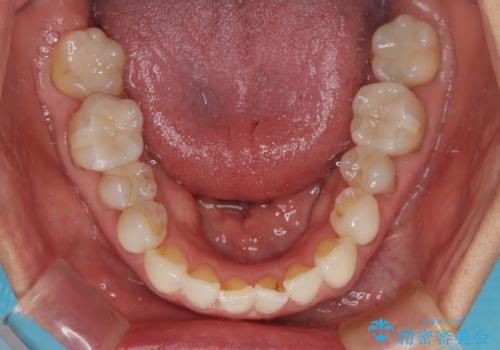

デコボコと銀歯 矯正治療とセラミック治療で綺麗な口元に

- 前歯のデコボコと口を開けたときに見える銀歯を気にして来院された患者様です。

ある程度デコボコが解消されれば大丈夫とのことで、インビザライン・モデレートパッケージを利用して歯列を整えて行くこととしました。

矯正治療後に銀歯をセラミッククラウンなどに置き換えていくと、どうしても後戻りを起こしてしまうため、矯正治療が概ね終了した時点で銀歯を全てセラミックとし、最後に仕上げでインビザラインにを用いて細かいデコボコを改善していくこととしました。

とても明るい口元となり、人目を気にせず、大きく口を開けて笑えるようになりました。